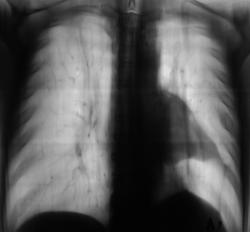

Пациент в 2008 году прошел плановую профилактическую флюорографию.

Сегодня, планово, регистратурой пациент был направлен на профилактическую флюорографию, предъявляет жалобы на наличие одышки.

Произведено дообследование.

Рентгенография и томография.

Плеврит.

Осумкованный пристеночный плеврит.

Пропунктировали, согласились "на осумкованный плеврит".

левосторонний плевральный выпот

Похоже на осумкованный, или как?